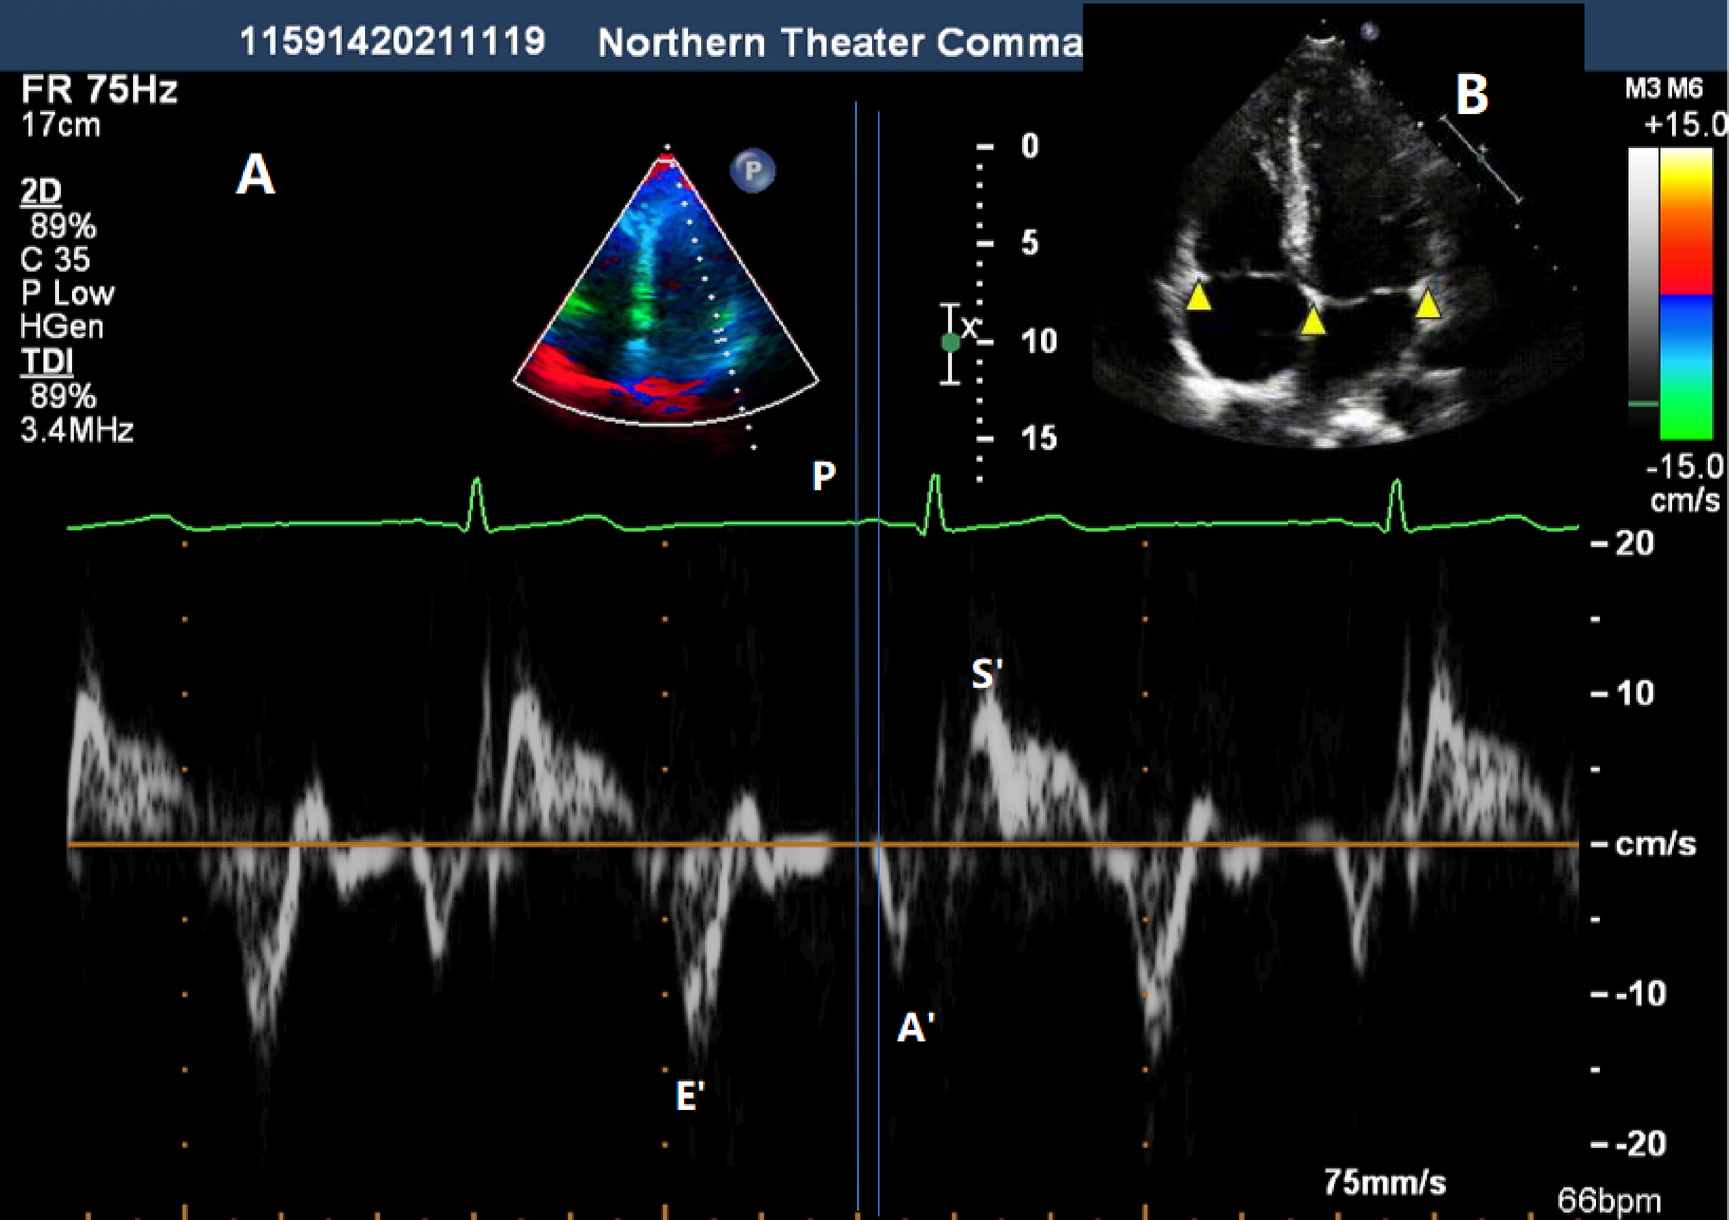

Fig. 3

By measuring the interval from the start of the P wave in the electrocardiogram to the start of the A´ wave in the TDI spectrum, the electromechanical coupling time can be obtained (A). The three arrows from right to left respectively represent the positions of the lateral wall of the mitral annulus, the interatrial septal annulus, and the lateral wall of the tricuspid annulus in the Four-chamber view (B).